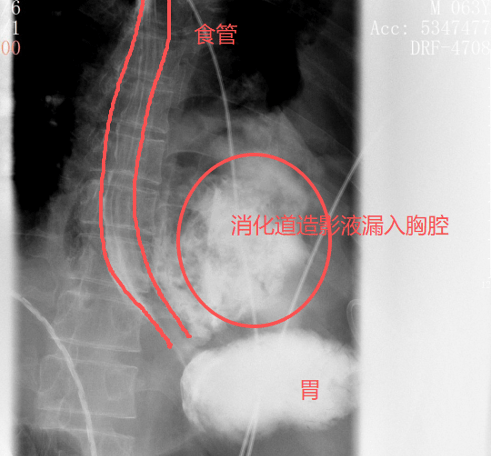

很快,口服钡(bei)餐的效果印证了他的判断:钡(bei)剂(ji)从(cong)食道下段的裂口处大量漏出,间(jian)接进入了左侧胸腔。

红圈(quan)区域是食物(wu)残渣、消化(hua)液破入食管